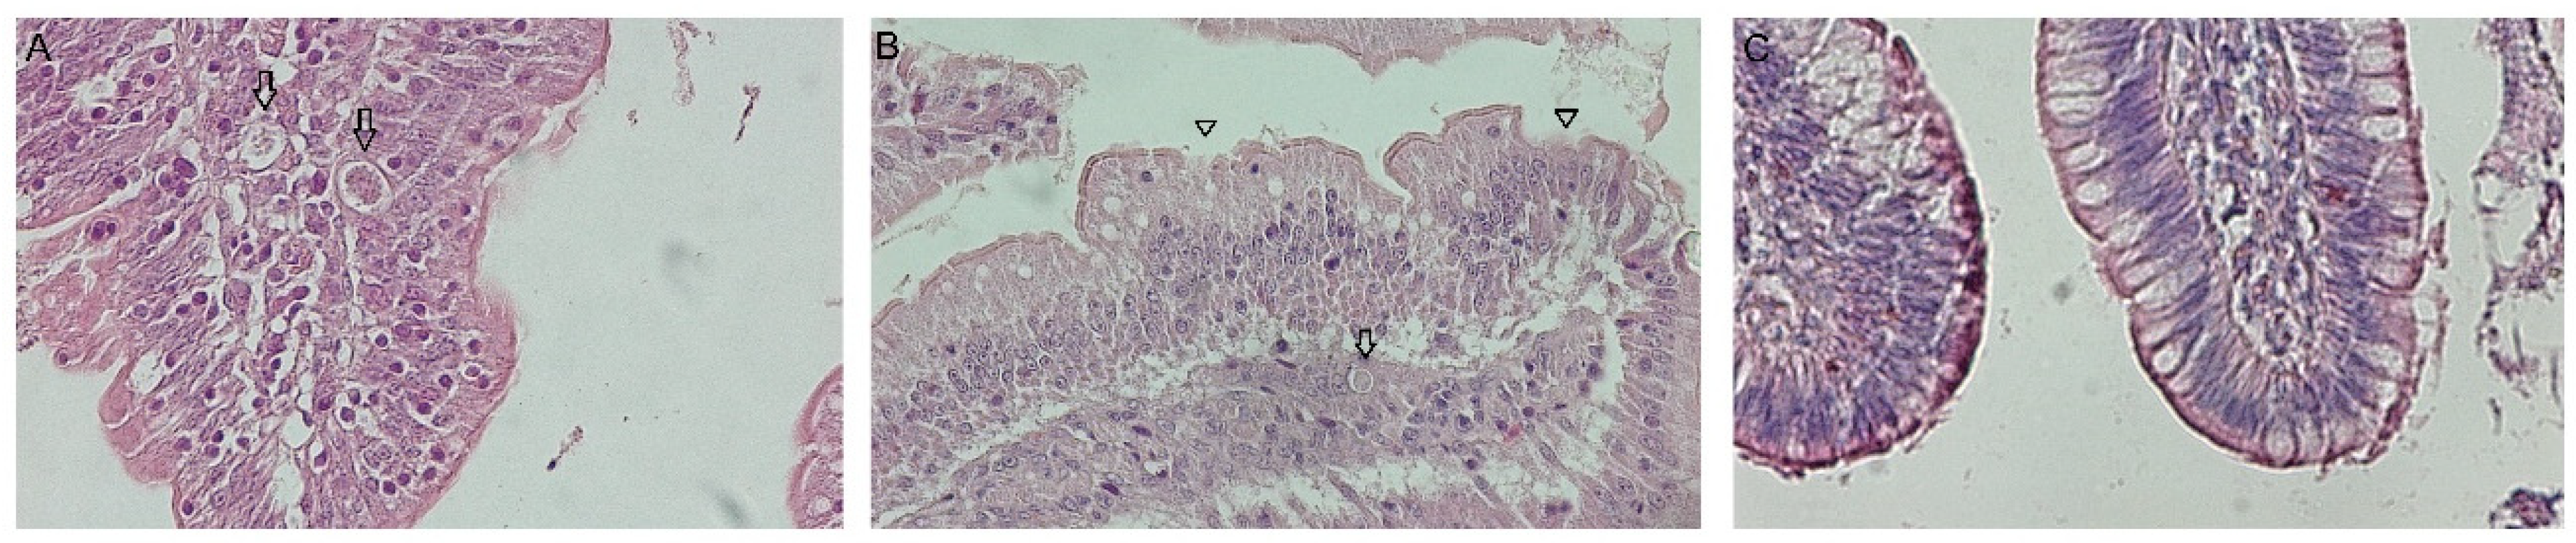

Villi damage and asexual stages of the parasite were observed in HE stains in all challenged groups (Figure 2A,B), and no particularities were observed in NC (Figure 2C). Additionally, changes in the VH (p < 0.05) were observed in the duodenum of challenged groups. The VH–CD ratio showed an alteration of the normal morphology of the duodenum among the challenged groups and the not in NC (Tukey’s test, p < 0.05), with HDG being the most affected (2.88) and LDG the least (3.78) (Table 2).

Figure 2.

Histological sections of the duodenum stained with hematoxylin and eosin (HE). (A) Eimeria-asexual stages (arrows) in IDG (images are representative). (B) Histological changes with affected villi (triangles) and Eimeria-asexual stages (arrows) in IDG. (C) Negative control with normal morphology. Total magnification 400×.

Furthermore, E. acervulina was the predominant species in the inoculum and parasitizes the duodenum, causing the shortening of villi and increasing crypt depth [28]. In this study, affected villi and asexual parasite stages were observed (Figure 2A,B), and it was also demonstrated that deeper crypts and shorter villi were found upon Eimeria challenge. The worst VH–CD ratio was 2.88 in HDG, indicating more damage than the other groups, probably affecting gut functionality. This aligns with previous findings in Hy-line Brown layers [29], Ross 308 broilers [30], and Yellow broilers [31], which indicates that Eimeria infection led to deeper intestinal crypts, decreasing the VH–CD ratio, demonstrating a slower enterocyte turnover. However, Belote et al., 2023 [32], have concluded that in broilers challenged with field Eimeria oocysts, the augmented villi size does not necessarily correlate with improved intestinal functionality when internal immune processes drive this enlargement. In contrast, the NC group showed that the best VH–CD ratio was 6.12. The ratio identified by De Verdal et al., 2010 [33] was 7.73 in the duodenum of a broiler line at 23 days, implying a greater rate of epithelial cell turnover in the proximal small intestine.